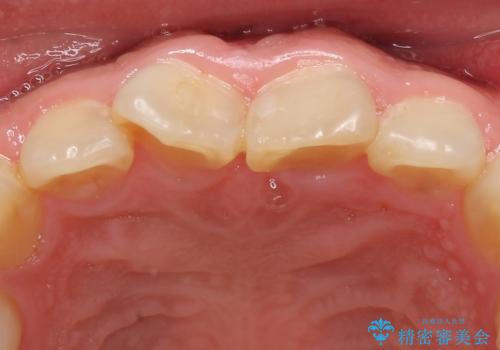

御希望された再根管治療終了後、オールセラミッククラウンによる補綴を行いました。

今回用いたオールセラミッククラウンはジルコニアフレームという白い素材の上にセラミックを盛っているため、審美性が非常に高いのが特徴です。

また、ジルコニアは人工ダイヤモンドの材料にも使われているほど高い強度を持っており、そのためオールセラミッククラウンは審美性だけでなく、奥歯やブリッジの補綴も可能とするクラウンです。